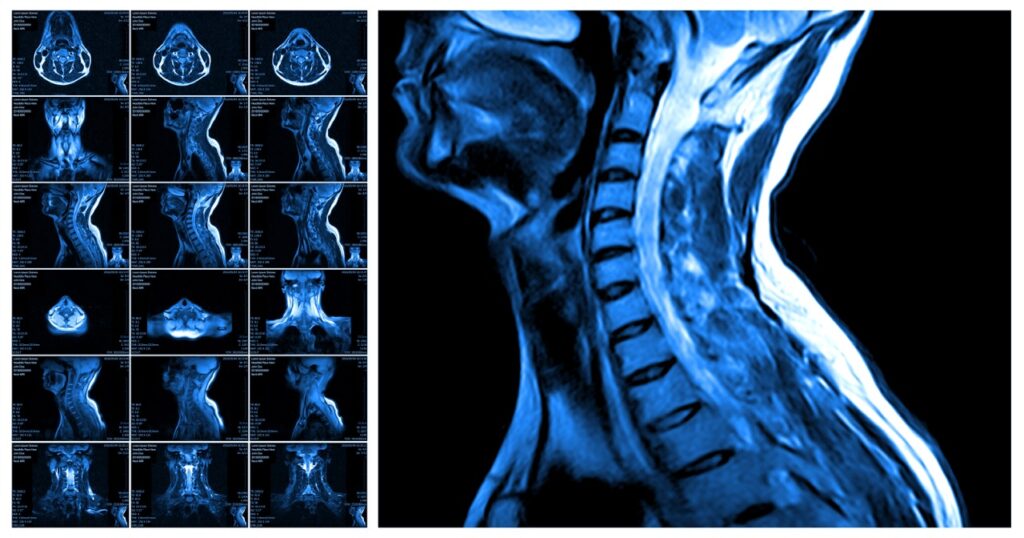

Spine MRI in Pembroke Pines: Fast Diagnosis for Back & Neck Pain

Fast Relief from Back and Neck Pain with a Spine MRI in Pembroke Pines Back and neck pain can control your entire day. You wake up stiff, struggle through work, and go to bed aching. When pain becomes a constant companion, you need answers fast. A spine MRI in Pembroke Pines provides the detailed imaging […]